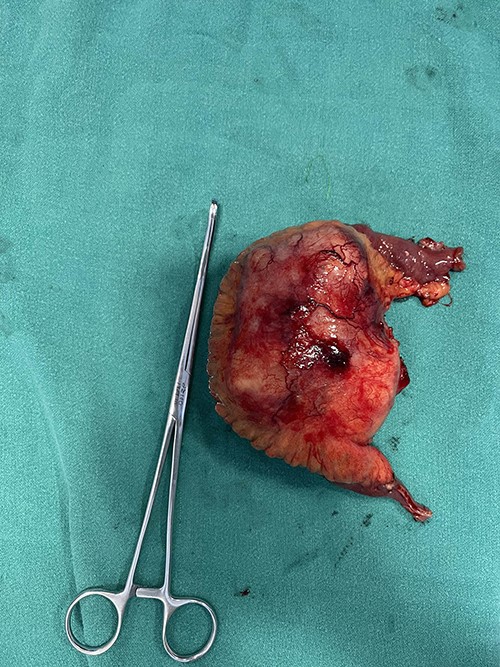

Patient was admitted. Midline laparotomy was done. Peritoneal cavity was explored. Large lipomatous mass measuring 13 cm × 8 cm was found at ileal mesentery at ~70 cm from ileocecal junction. Mass was well defined with invasion into the bowel and the ileal arteries. Mass was excised in toto along with involved ileum attaining macroscopically negative margins. Bowel continuity was maintained with end-to-end anastomosis (Fig. 3). Postoperative period was uneventful.